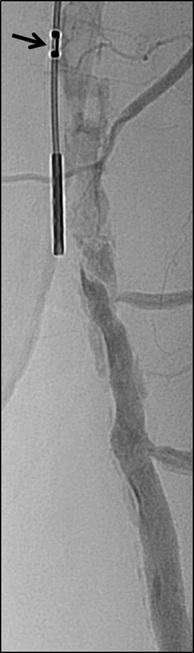

n PERIPHERAL ARTERIAL DISEASE:

Crossing chronic total occlusion lesions are challenging procedures. The BeBack crossing catheter—Bentley’s first product to be available in both Europe and the USA following the company’s acquisition of Upstream Peripheral Medical Technologies’ GoBack crossing catheter in September 2022— offers a new solution in this space. In a Bentleysponsored advertorial, Andrej Schmidt (Leipzig, Germany) shares his clinical experience with the BeBack, noting how it has been a “gamechanger” in his endovascular peripheral arterial disease practice.

For more on this story go to page 19.